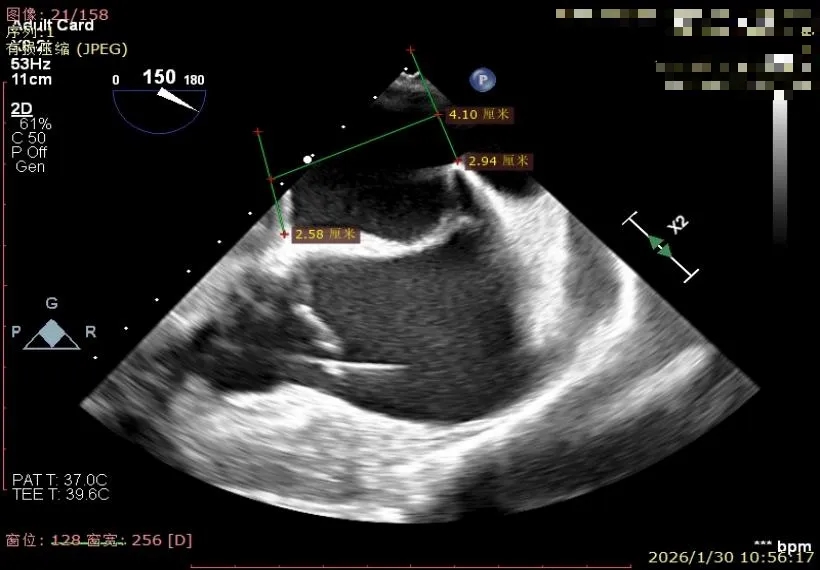

经食道超声精细化测量:肺静脉逆流,房间隔可穿刺高度约4.2cm,Flail宽度约21mm,Flail高度约8mm,Flail Gap约4mm, 3区AML长约23mm、PML长约12mm、2区AML约32.2mm,PML约16mm。

房间隔可穿刺高度约4.2cm

Flail宽度约21mm,Flail高度约8mm